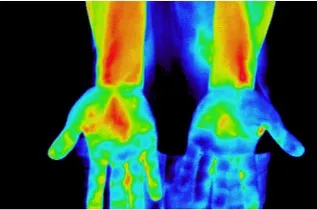

1 血流促進効果

シリカ含有率の高いオーガニック炭がもたらす輻射熱とラジウムなどの温泉鉱石により、広範囲の血流を促進します。(主要血管部を含む体表温度の変化により測定)

スパオール装着時の左右の手の温度分部

スパオール装着時の上半身の温度変化